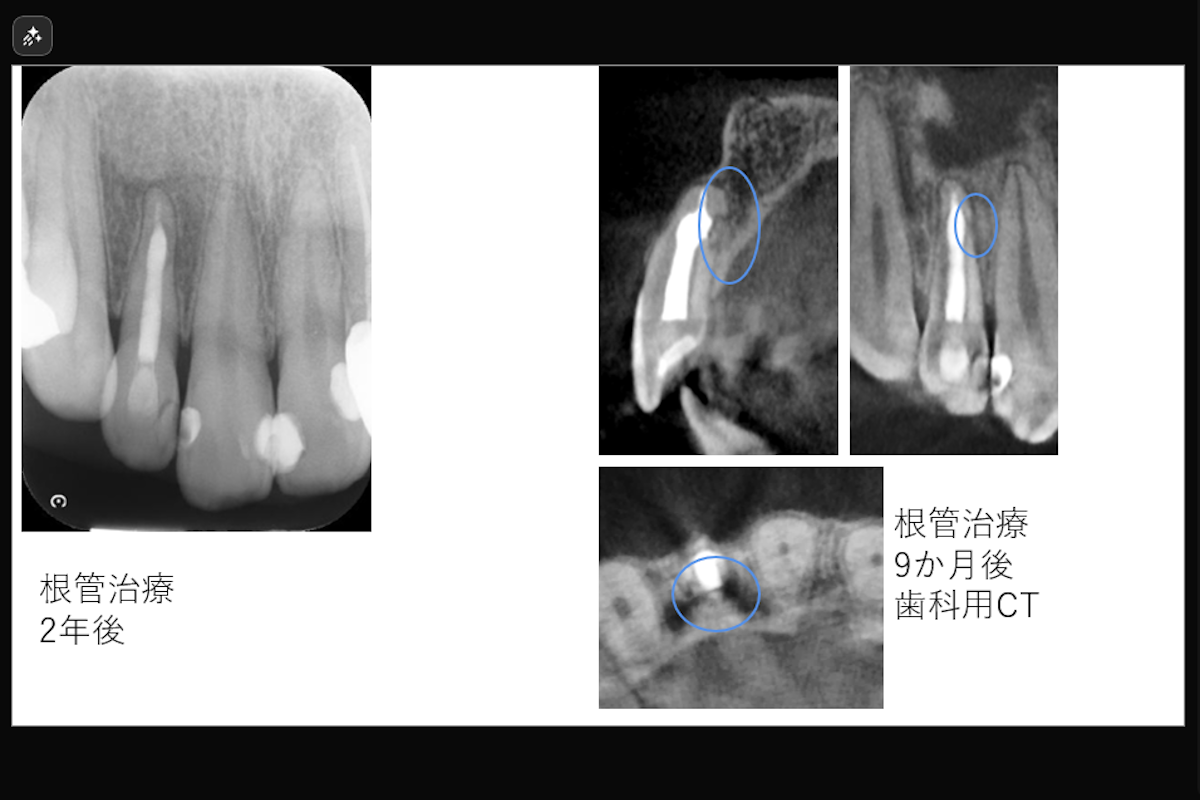

- 治療期間: 約1.5か月

- 治療回数2回

- 治療内容: 上顎右側側切歯 根管治療(レーザーを用いた根管洗浄、MTAを用いた根管充填)

- 治療のリスク: 残存歯質の厚みによって歯根破折のリスク、経過によっては外科的歯内療法